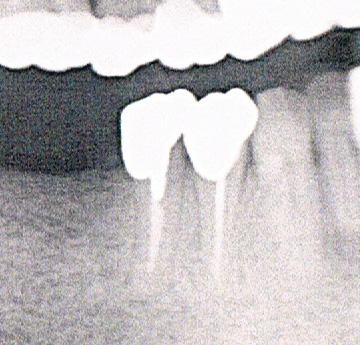

根管治療

根管治療とは、歯の根っこ(根管)の中の細菌に感染した部分を除去し、修復する治療です。

根管内を十分に殺菌・洗浄したのち、再び細菌感染を起こさないように根管に薬剤を充填します。

根管は人それぞれ形態異なり、根の先が分かれていたりと非常に複雑な形状をしています。ですので、根管治療には高い精密さが求められます。

根管治療を行うことで歯を抜かずになるべく自分の歯を残すことが可能になります。